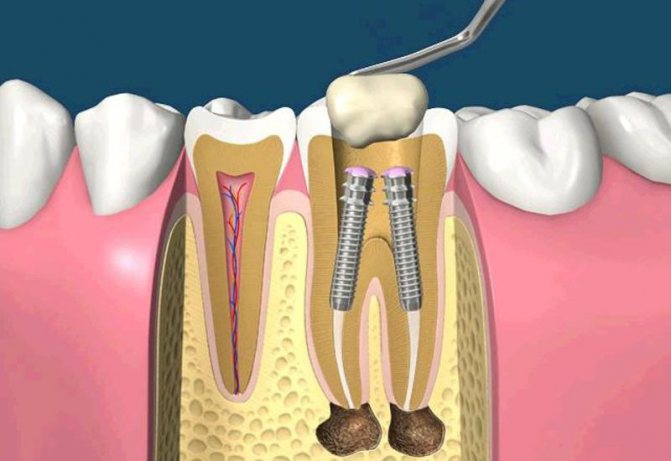

Для восстановления и исправления зубов сегодня разработаны десятки методов, каждый из которых призван быстро и безболезненно решать определенную клиническую задачу. При кариозных разрушениях лучше всего себя зарекомендовали вкладки, а при отсутствии у зуба опоры на помощь приходят штифты. Установка штифта при зубном протезировании осуществляется следующим образом: один конец стержня вкручивают в корневой канал, на другом крепят новый красивый зуб.

Речь идет конструкции в виде стержня, который фиксируется в корневом канале разрушенного зуба. Он служит элементом, обеспечивающим надежное сцепление корневой системы с композитным материалом или искусственной коронкой. Использование подобного штифта позволяет восстановить коронковую часть зуба при наличии живого корня в удовлетворительном состоянии. Прежде чем произвести установку такой конструкции, врач должен принять во внимание следующие моменты:

После всех подготовительных мероприятий, диагностики и выбора тактики лечения, врач приступает непосредственно к процедуре. Для начала изолируются соседние зубы, проводится удаление старого пломбировочного материала или пораженных кариесом тканей, лечение и подготовка зубного канала, его расширение при необходимости, а также полная антисептическая обработка тканей. Далее обычно следует примерка – врач фиксирует временное изделие и направляет пациента на снимок, чтобы убедиться, что элемент установлен в правильном положении и на требуемую глубину. Если все хорошо, временную конструкцию извлекают и устанавливают постоянную.

Сам стержень аккуратно размещают в корневом канале с помощью специального ключа, который обычно поставляется в комплекте. Модель с резьбой вкручивают с особой осторожностью во избежание повреждения стенок канала. Пассивная вариация менее требовательна в этом отношении, а для ее надежной фиксации используется цементный состав. Верхушка стержня остается над линией десны и служит основой для фиксации коронки. Все манипуляции проводятся под местной анестезией.